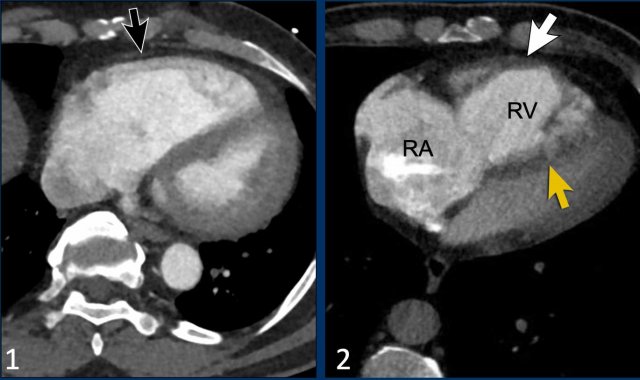

Here we have two examples of patients with pulmonary emboli and cardiac remodelling.

Images

1. There is right ventricular dilatation with septal flattening, but no evidence of RV wall hypertrophy (black arrow), consistent with an acute increase in RV afterload.

This can be seen in patients with acute pulmonary embolism.

2. In contrast, in this patient there is dilatation of the right ventricle and atrium with interventricular septal flattening, accompanied by RV wall thickening (white arrow).

This suggests chronic pressure overload and is indicative of longstanding pulmonary hypertension.

This can be seen in patients with chronic thromboembolic pulmonary hypertension.